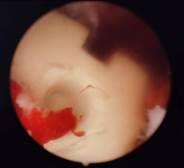

术中在内镜下行椎弓根螺钉置入术